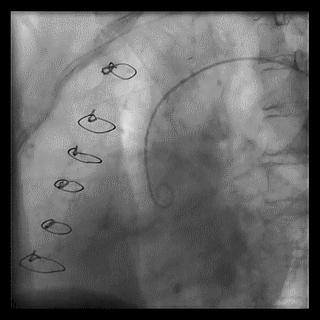

2.安全方面考虑

(1)导管总进圆锥动脉

➢ CASE 8

必要时更换导管,避免并发症的发生

(2)口部病变

应换短头、小号导管,轻柔少量注射对比剂